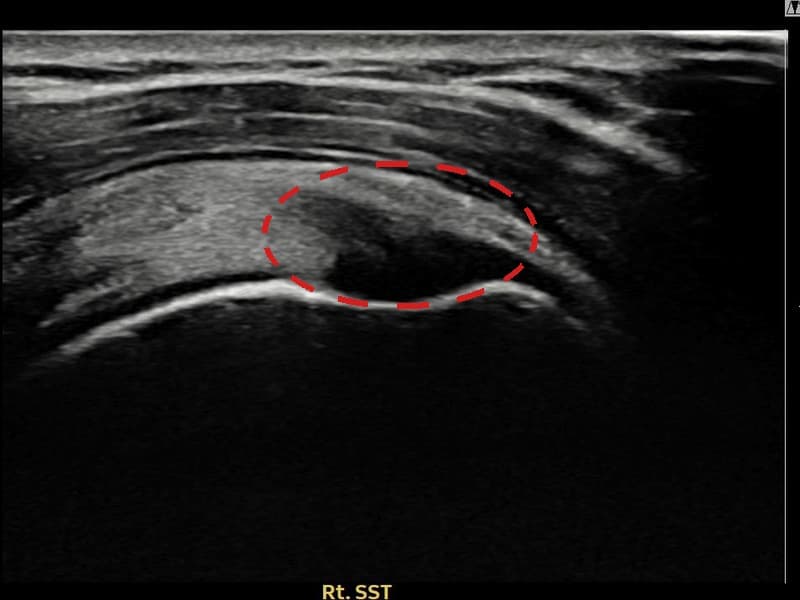

시술 전 초음파 측정 결과 파열 크기는 7mm × 4mm (힘줄 두께의 약 42% 결손)로 확인되었습니다. 시술 전 초음파에서 우측 극상근건 관절면측의 에코 단절과 힘줄 내부 결손 소견이 명확히 관찰되었으며, 힘줄 두께가 반대측 대비 현저히 감소된 상태였습니다. 시술 후 초음파에서 극상근건의 연속성이 회복되고 내부 에코 패턴이 균질하게 개선되어 파열 부위의 구조적 재생이 확인되었습니다.

50대 중반 여성 환자분으로, 꽃꽂이 강사로 활동하시며 팔을 앞·위로 반복적으로 뻗는 동작을 오랫동안 해오신 분이었습니다. 처음에는 수업 중에만 통증이 있었으나 점차 머리 감기, 선반 정리 등 일상 동작에서도 불편감이 생겨 내원하셨습니다. 초음파 검사에서 우측 극상근건 관절면측의 부분파열이 확인되었으며, 파열 범위와 위치를 고려해 초음파 유도 하 축소봉합술을 시행하였습니다. 시술은 30분 이내에 완료되었고 당일 귀가하셨으며, 시술 후 4주간 팔을 어깨 위로 올리는 동작을 제한하고 단계적으로 가동 범위를 늘려 나갔습니다. 시술 13주 후 추적 초음파에서 극상근건 연속성이 완전히 회복되고 에코 패턴이 정상화된 것이 확인되었으며, 통증 없이 강의에 복귀하셨습니다.